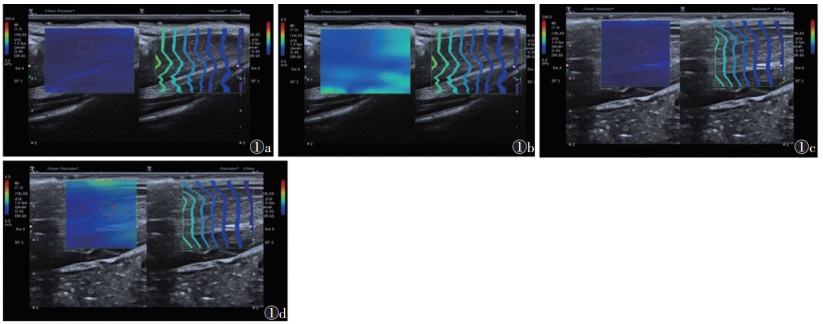

大鼠进入麻醉期后,下肢取自然位(踝关节屈曲约90°),厚涂耦合剂,探头轻放在足三里穴区,避免下肢肌肉受压。根据足三里穴局部肌肉解剖,超声探头长轴与大鼠腓肠肌肌束方向平行的状态下,开启剪切波弹性模式。在腓肠肌定位基础上,探头向小腿前外侧平移,即可定位胫骨前肌。选取肌腹中段较厚部位为弹性成像ROI,ROI直径2 mm,深度0.5~1.0 cm[8](图 1)。连续观察在LIPUS刺激后20 min内穴位周围肌肉弹性值,每隔30 s测量1次组织弹性图,测量3次取平均值。

| 注:图1a为测量胫骨前肌剪切波速度,图1b为测量胫骨前肌杨氏模量值,图1c为测量腓肠肌剪切波速度,图1d为测量腓肠肌杨氏模量值;ROI直径为2 mm,测量深度为0.5~1.0 cm 图 1 剪切波弹性技术测量肌紧张度 |